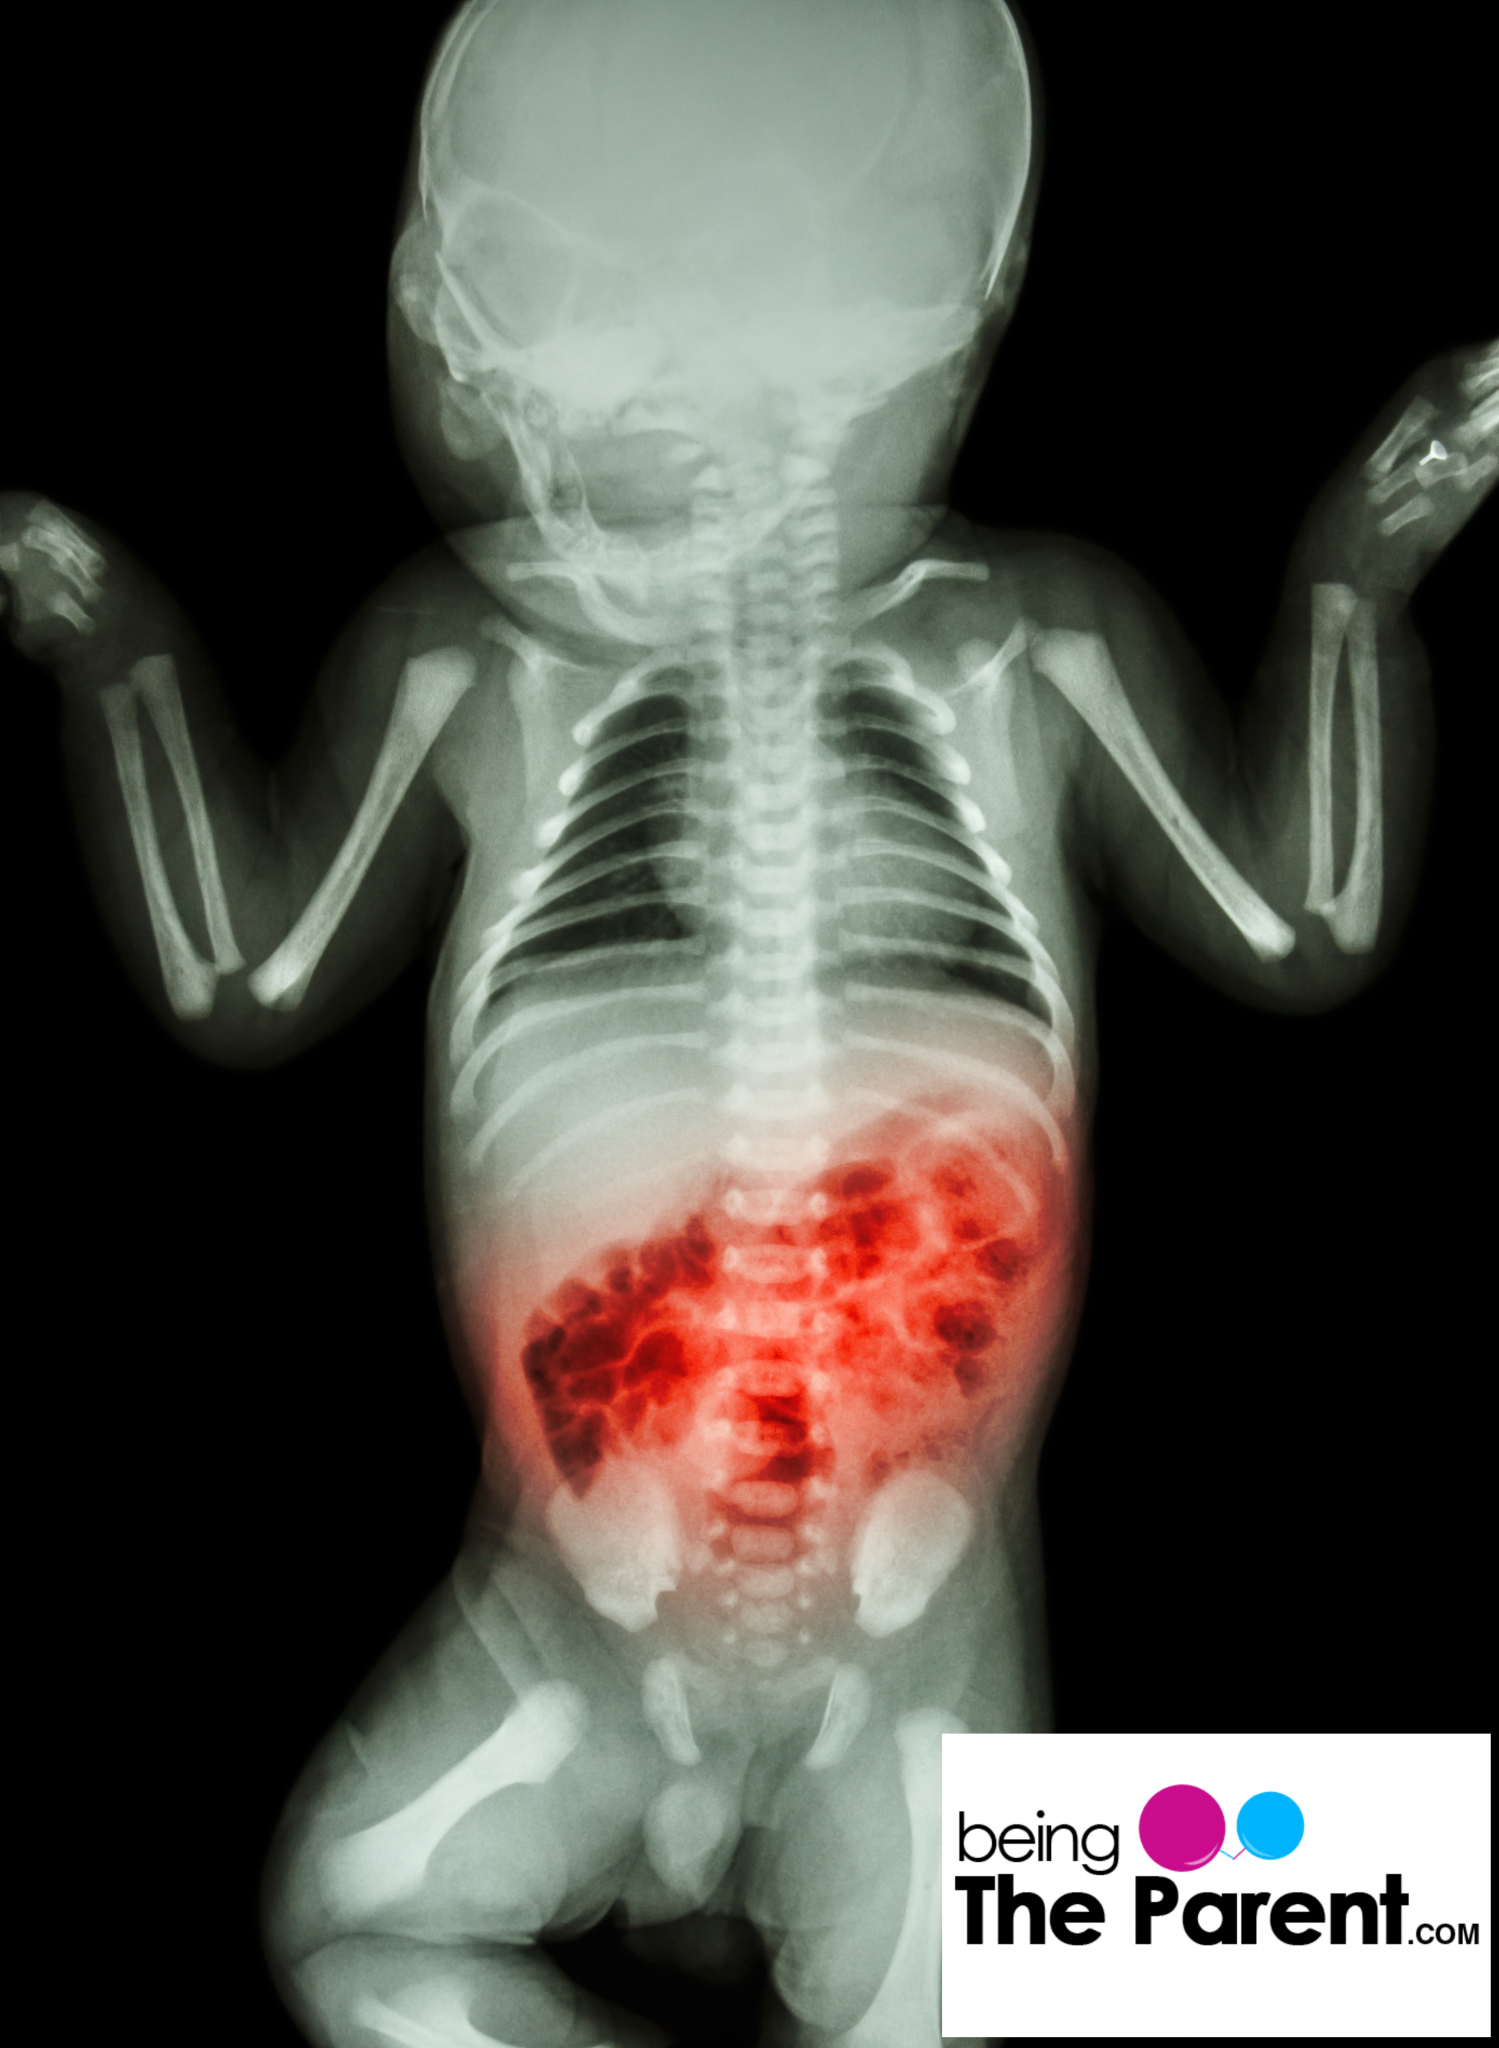

From www.beingtheparent.com

Necrotizing Enterocolitis Causes, Symptoms, and Treatment Being The Bloody Stools Enterocolitis common causes of enteritis and colitis include viral infections, such as the stomach flu, parasite infections, like giardiasis, and bacterial infections,. These cases may require extensive enterectomy and the formation. the blood often shows up in stool or vomit but isn't always obvious. necrotizing enterocolitis (nec) often is associated with extensive bowel necrosis. Stool may look black. Bloody Stools Enterocolitis.